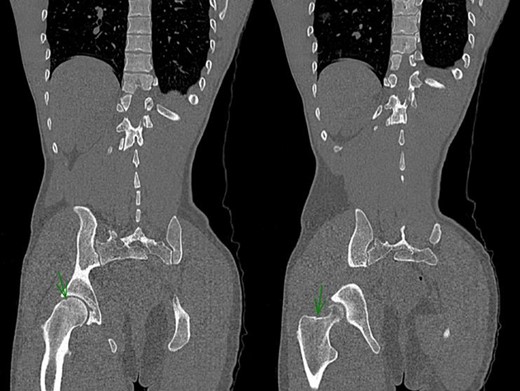

After reduction, the neurovascular examination remained normal. Pelvis CT-scan was performed and showed a bifocal fracture of the hip associating a non-displaced inter-trochanteric fracture and a non-displaced capital fracture (Fig. 2). Patient was discharged on day 5 with strict bed rest for 6 weeks.

Post-reduction CT-Scan of the pelvis showing a non-displaced fracture of the head of the femur and a non-displaced inter-trochanteric fracture of the right hip.

CT is advised to rule out any associated injury, but it should never delay reduction. Such delay has been associated with worse prognosis and increased incidence of avascular necrosis. Joint reduction can be achieved under general anesthesia (GA) by maintaining traction towards the head while gradually extending the thigh, sometimes with additional internal rotation. In our case, CT-Scan was performed after hip reduction to rule out any associated injury. It showed a bifocal non-displaced fracture of the hip associating an inter-trochanteric fracture and a capital fracture. The exact timing of the fracture remained unknown. We could not identify whether the initial trauma was the cause of the fracture or the reduction manoeuver.